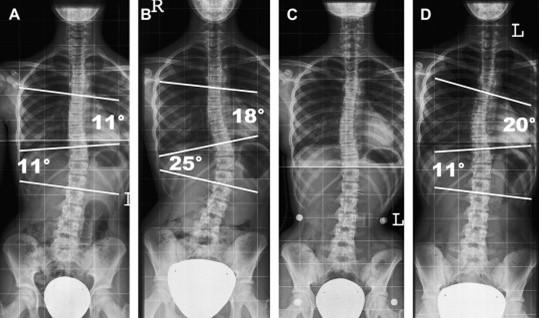

انحراف ایجاد شده در اثر اسکولیوز ممکن است در ناحیههای توراسیک یا لومبار رخ دهد. البته برخی اوقات اسکولیوز ممکن است که با دو یا سه انحراف، هر دو ناحیه را بهصورت همزمان درگیر کند. انحراف و انحنای ستون فقرات معمولاً یا به سمت راست اتفاق میافتد یا به سمت چپ. هر کدام از این انحرافها ممکن است بخشی از بدن را تحتتأثیر قرار دهند. اسکولیوز با تحدب به چپ یا لووسکولیوز (Levoscoliosis) به شکل C و اسکولیوز با تحدب به راست یا دکسترواسکولیوز (Dextroscoliosis) به شکل C برعکس است دیده میشود. چهار نوع رایج اسکولیوز بر اساس محل انحراف شامل موارد زیر میشوند:

- اسکولیوز توراسیک (Thoracic): ناحیه توراسیک در بین شانهها و پشت قفسه سینه قرار دارد. در این نوع اسکولیوز، انحراف به طرفین در میان شانهها اتفاق میافتد و باعث بروز تغییرات و جابهجایی استخوانها در قفسه سینه و کتف میشود.

- اسکولیوز لومبار (Lumbar): به ناحیه فوقانی و پایینی کمر، لومبار گفته میشود. در این نوع از اسکولیوز، انحراف به طرفین در پایین کمر اتفاق میافتد و باعث ایجاد تغییرات در شیوه راهرفتن و ناترازی لگن میشود.

- اسکولیوز توراکولومبار (Thoracolumbar): این نوع از انحراف هر دو قسمت توراسیک و لومبار را درگیر میکند و انحراف از قسمت شانهها شروع شده و تا پایین کمر ادامه دارد.

- اسکولیوز دوگانه: در این نوع از اسکولیوز، ستون فقرات در دو نقطه منحرف میشود. بیشتر اوقات این انحرافها باعث میشوند تا ستون فقرات به شکل S دیده شوند.

شدت اسکولیوز به میزان انحنا و پیچش ستون فقرات بستگی دارد. بهطور کلی، اسکولیوز به سه دسته تقسیم میشود: خفیف (کمتر از ۲۵ درجه)، متوسط (بین ۲۵ تا ۴۵ درجه)، و شدید (بیش از ۴۵ درجه). در درجات خفیف، معمولاً علائم کم و درمانهای غیرجراحی مانند فیزیوتراپی و بریس مؤثر هستند. در درجات متوسط، نیاز به مراقبتهای بیشتر و گاهی استفاده از بریس وجود دارد. در درجات شدید، جراحی معمولاً پیشنهاد میشود، زیرا ممکن است مشکلاتی چون درد مزمن، مشکلات تنفسی یا آسیب به اندامهای داخلی پیش آید.

اسکولیوز خفیف

اسکولیوز خفیف به حالتی اطلاق میشود که انحنای ستون فقرات کمتر از ۲۵ درجه باشد. این نوع اسکولیوز معمولاً علائم کمتری دارد و در بسیاری از موارد به صورت تصادفی در معاینه پزشکی یا تصویربرداریهای مربوط به دلایل دیگر شناسایی میشود. افراد با اسکولیوز خفیف ممکن است هیچ دردی احساس نکنند و از نظر عملکرد جسمی محدودیتی نداشته باشند.

اسکولیوز متوسط

اسکولیوز متوسط به حالتی گفته میشود که انحنای ستون فقرات بین ۲۵ تا ۴۵ درجه است. در این حالت، انحنای ستون فقرات بیشتر از حد طبیعی است و ممکن است علائمی مانند درد خفیف تا متوسط، احساس عدم تعادل یا فشار بر روی اندامهای داخلی مانند ریهها مشاهده شود. اسکولیوز متوسط معمولاً نیاز به درمانهای فعالتری مانند استفاده از بریس، فیزیوتراپی و پیگیری منظم دارد تا از پیشرفت بیشتر جلوگیری شود.

اسکولیوز شدید

اسکولیوز شدید به حالتی اطلاق میشود که انحنای ستون فقرات بیش از ۴۵ درجه است. در این وضعیت، انحنای ستون فقرات میتواند به شدت بر عملکرد بدن تأثیر بگذارد و مشکلاتی جدی مانند درد مزمن، فشار بر ریهها و قلب، و محدودیتهای حرکتی ایجاد کند. در این مرحله، درمانهای غیرجراحی معمولاً مؤثر نبوده و جراحی برای تصحیح انحنا و جلوگیری از مشکلات بیشتر، مانند آسیب به اندامهای داخلی، غالباً توصیه میشود.

برای اندازهگیری شدت اسکولیوز زاویه کاب (Cobb Angle) را محاسبه میکنند. در این روش دو خط از شروع و پایان انحراف با همان زاویه میکشند و سپس آن دو خط را بهوسیله دو خط قائم دیگر به یکدیگر وصل میکنند. زاویهای که میان خطوط جدید شکل میگیرد، نشاندهنده میزان شدت انحراف است. در موارد بسیار خفیف، به دلیل زاویه کم، حتی ممکن است که تغییرات ظاهری در کمر و ستون فقرات مشاهده نشود، اما در موارد شدید علائمی مانند عدم تقارن شانهها یا لگن و همچنین برجستگی کتف در یک سمت مشاهده میشود.